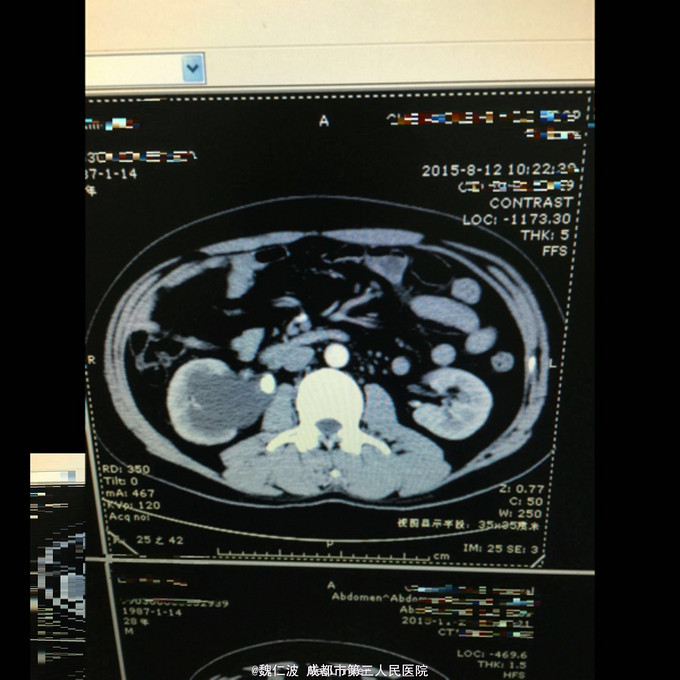

右侧输尿管结石碎石术后3月,发现右侧输尿管上段闭锁4天 3月前因右侧输尿管上端结石行输尿管软镜钬激光碎石,术后恢复可,但拍石稍差,1月后取支架管,术后2月复查右侧肾积水1厘米,3月复查积水5Cm,外院行右肾穿刺造瘘术,发现右侧输尿管上端闭锁,遂来我院。

造瘘管通畅,尿液淡黄。余无特殊。 辅助检查尿常规正常,右侧肾盂尿白细胞2+。

右侧输尿管上端闭锁,右肾结石,右侧输尿管上端结石 经抗感染治疗后,行开放狭窄段切除,输尿管吻合术,安置F8输尿管支架管。